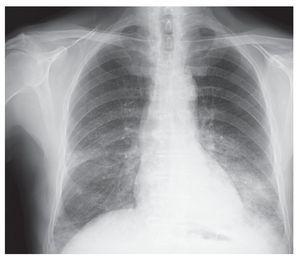

Derrame pleural masivo secundario a pseudoquiste pancreático

Salinas Lasa, Iturbe Susilla, Díaz Urquizo, Ponce Sánchez, Bustamante Madariaga, Crespo Notario

Revista de Patología Respiratoria 2011;14:104-5

Acceso a texto completo